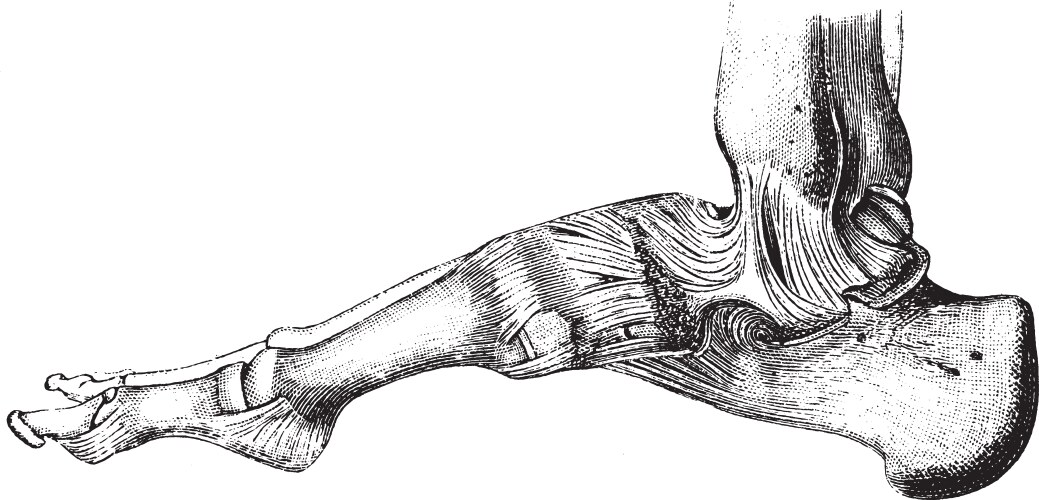

- Running

- Ankle

- Anatomy

- Sprain

- Skeletal

- Illustration

- Injury

- Medical

- Science

- Anatomical

- Arthritis

- Biology

- Bone

- Diagnosis

- Foot

- Graphic

- Health

- Human

- Inflammation

- Joint

- Leg

- Metatarsal

- Pain

- Skeleton

- Therapy

- Walk

- Ache

- Athlete

- Bones

- Condition

- Exam

- Injured

- Lateral

- Painful

- Plantar

- Procedure

- Structure

- Symptoms

- Talus

- Toe

- Transparent